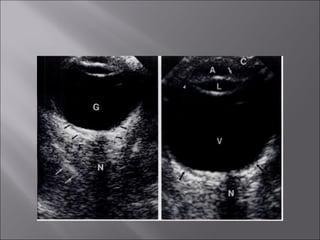

Ultrasound and CT scans provide anatomical images of the orbit, while color Doppler imaging provides visualizations of vascular structures and blood flow within lesions. These imaging techniques are used to evaluate a variety of orbital conditions involving blood vessels, infections, tumors, congenital issues, trauma, and more, and can help identify vascular disorders, thrombosis, treatment responses, and dynamic changes in benign tumors over time.